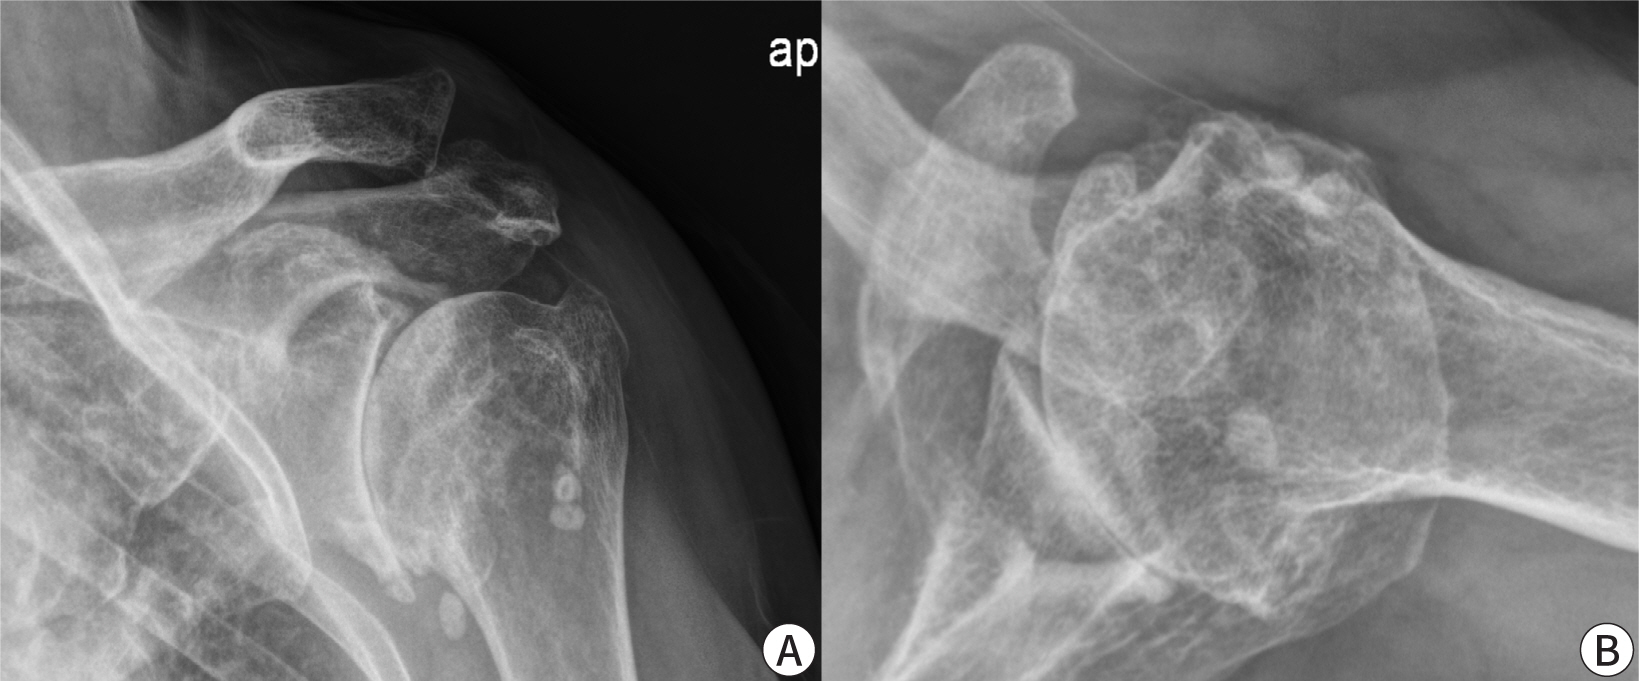

Initial evaluation of a patient with shoulder pain and dysfunction should always include a complete set of plain radiographs of the shoulder. These are essential for assessing potential causes of pain and for evaluating conditions such as osteoarthritis, superior migration of the humeral head, avascular necrosis, osteoporosis, or tumors (Fig. 2). A supraspinatus outlet view may be particularly useful for visualizing bony structures involved in scapulohumeral motions, such as bony spurs or ligamentous calcifications that could impinge on the underlying rotator cuff. An axillary view is beneficial for ruling out shoulder dislocation in cases of trauma. The rotator cuff can be examined using ultrasonography (US) or MRI. US is cost-effective and allows for real-time examination of the shoulder joint by the physician. It can determine the size and location of tears, although the results are highly subjective and depend on the operator [10]. A study found that preoperative US identified mixed hyperechoic and hypoechoic foci in the supraspinatus tendon with a sensitivity of 93%, a specificity of 94%, a positive predictive value of 82%, and a negative predictive value of 98%. MRI is considered the gold standard for imaging the rotator cuff tendons [13]. It provides a comprehensive assessment of the entire rotator cuff musculotendinous unit (Fig. 3). The presence of muscle atrophy and fatty infiltration can indicate the chronicity of tears, aiding in treatment decisions. Another study showed that MRI and US have similar diagnostic accuracy for detecting full-thickness RCTs. However, it noted that US had lower sensitivity than MRI in evaluating partial-thickness tears [14]. A diagnosis of partial-thickness tears is made when there is no evidence of tendon discontinuity on T1-weighted images, and MRI shows an increased signal in the rotator cuff. A partial-thickness RCT appears as an increased signal on T2-weighted images with a focal defect that is either intra-tendinous or limited to one surface and does not extend through the entire tendon. Rotator cuff tendinitis may cause increased rotator cuff signal and reduced anatomical definition on T1-weighted and proton density images, similar to the appearance of partial-thickness RCT. However, tendinitis is differentiated from partial-thickness RCT by the presence of only moderate or decreased signal on T2-weighted images [15].

Fig. 2.

The presence of osteophytes on the greater tuberosity and acromion of the humerus indicates that there is a high possibility of a rotator cuff tear. Provided by the authors.